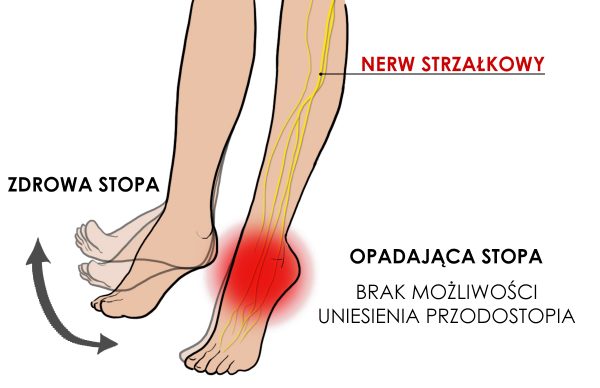

Opadająca stopa to schorzenie neurologiczne, uniemożliwiające uniesienie przodostopia. Powoduje ono, że palce ocierają o podłoże w trakcie chodu, dlatego pacjenci cierpiący na to schorzenie, często kompensują sobie dysfunkcję poprzez wysokie unoszenie kolana lub odwodzenie kończyny po łuku.

Generalnie opadająca stopa jest wynikiem wiotkości lub paraliżu mięśni prostowników stopy. Wyróżniamy 3 główne przyczyny:

- uraz nerwu strzałkowego

- uszkodzenie mózgu lub kręgosłupa

- uszkodzenie mięśni

Nerw strzałkowy unerwia ruchowo grupę przednią mięśni podudzia i grzbietu stopy (prostowniki). Jego uraz to najczęstsza przyczyna opadającej stopy. Ze względu na swój przebieg bardzo łatwo go uszkodzić w skutek np. urazu sportowego czy operacji w okolicy kolana.